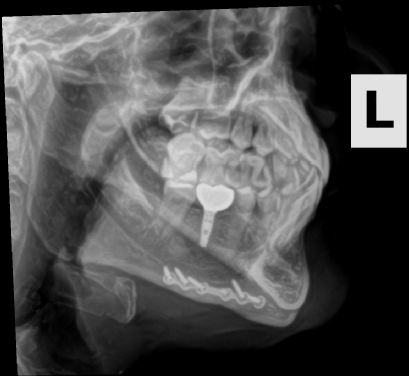

The story of how I got the x-ray or at least the whole scenario was kind of funny. I broke my pinky somehow at my friend's house in Oklahoma in the fall of 2023. When I went to the doctor they did an x-ray of my hand. I have a few metal parts in my head and then told them I got into a fight and thought I may have hurt some implants in my head. Not really but I just wanted these X-rays.